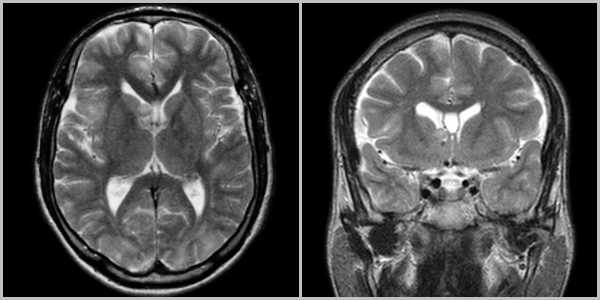

(а) МРТ, постконтрастное TIBIA, режим подавления сигнала от жира, аксиальный срез: у пациента с НФ1 и двусторонними глиомами зрительных нервов визуализируется характерная конфигурация внутриглазничной части зрительных нервов в виде букв "i", обусловленная их перегибом и удлинением в участке проксимальнее к глазному яблоку.

(б) МРТ, постконтрастное Т1-ВИ, режим подавления сигнала от жира, корональный срез: определяется выраженное контрастирование глиомы зрительного нерва.

Пилоцитарные астроцитомы зрительных нервов характеризуются вариабельной степенью контрастного усиления: от его отсутствия до высокоинтенсивного контрастирования. ПА зрительных путей часто сочетается с НФ1.